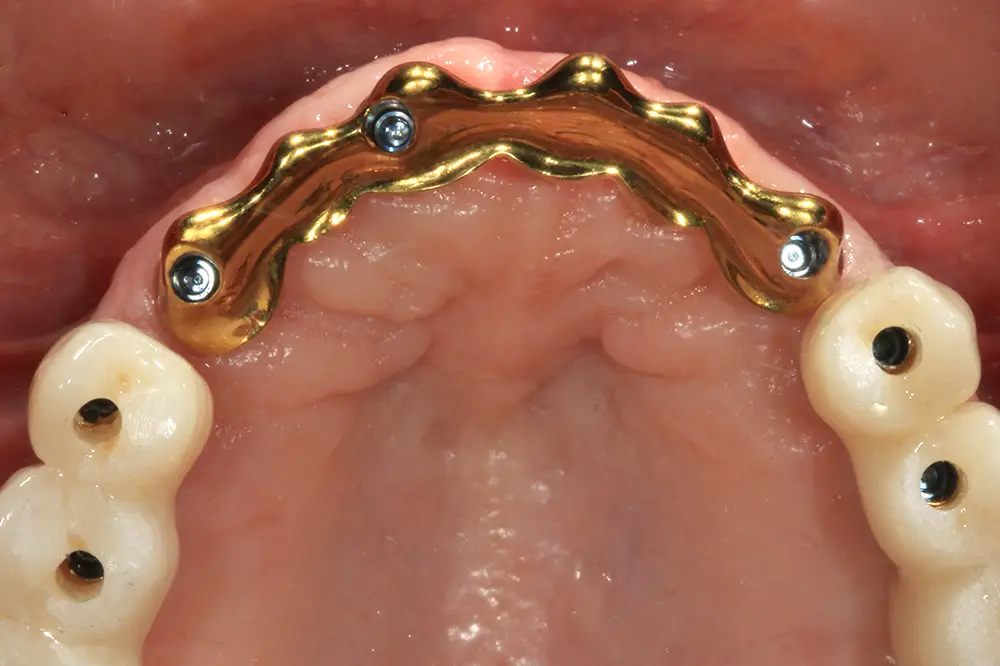

En el diseño de la prótesis final, se optó por la realización de una prótesis en tres tramos. En la zona anterior, se diseñó una barra Blender debido a las ventajas biomecánicas y protésicas que ofrece frente a una estructura metal-cerámica convencional. Para la confección de esta prótesis del sector anterior, se digitalizaron los modelos maestros con un escáner de sobremesa 3Shape F8 (3Shape, Copenhague, Dinamarca), generando archivos STL. El diseño de la estructura metálica tipo Blender se realizó mediante software Blenderfordental® (Blenderfordental, UAE), para configurar una estructura de titanio grado V (espesor mínimo 1,5–2,0 mm) con espacio higiénico mínimo de 1 mm. Se diseñaron e incorporaron macroretenciones y, tras confirmar el ajuste pasivo entre la estructura de titanio y el recubrimiento fresado de zirconio, la estructura se sometió a un tratamiento de nitrurado para su finalización (figs. 41-44).

Figs. 41 y 42. Confección, nitruración y prueba en el modelo maestro de la barra tipo Blender.

Figs. 43 y 44. Prueba de la estructura en la paciente, al igual que las prótesis del sector posterior para garantizar el correcto ajuste.

La estructura metálica de titanio y el recubrimiento fresado de zirconia se confeccionaron de forma paralela y simultánea a partir de los mismos archivos CAD. Las estructuras se fabricaron mediante fresado CAD/CAM de 5 ejes en titanio grado 5 (Ti-6Al-4V) (HTL Cad-Cam Lab, Vitoria, España). Una vez acabadas ambas piezas, se realizaron los ajustes finos necesarios hasta obtener un asentamiento pasivo y congruente entre la estructura y el recubrimiento. A continuación, la estructura metálica se envió a nitrurar y, tras el tratamiento, el recubrimiento de zirconia se cementó sobre la estructura empleando un cemento de resina autoadhesivo RelyX™ Unicem 2 Automix (3M ESPE, Seefeld, Alemania), cemento de resina autoadhesivo de curado dual siguiendo el protocolo e indicaciones del fabricante (figs. 45 y 46).